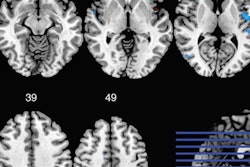

Brain MR images plot the average cerebral blood flow (left panel) and gray-matter volume fraction (right panel) for athletes with and without a history of concussion. Red arrows denote areas where concussed athletes showed significantly lower blood flow and gray-matter volume. Images courtesy of Nathan Churchill, PhD, and St. Michael's Hospital.Researchers also found reduced gray-matter volume in the temporal lobes, supplementary motor area, and the anterior cingulate. The deficiencies were associated with a longer recovery time among concussed athletes.